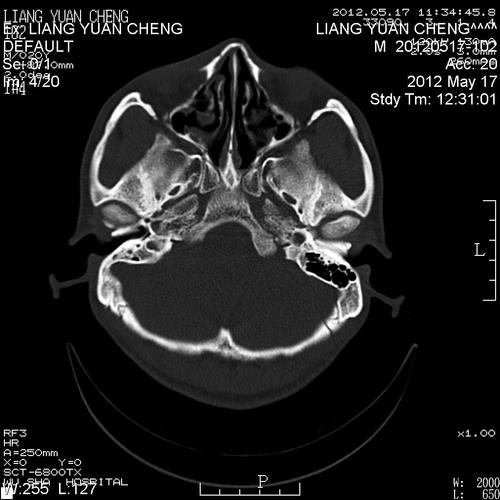

鼻骨骨折片子,鼻骨骨折图片

帮忙看下这个ct片子诊断是鼻骨骨折请问是什么性质的骨折

ct38674:鼻骨骨折吗?

鼻骨骨折ct

鼻骨骨折ct图片